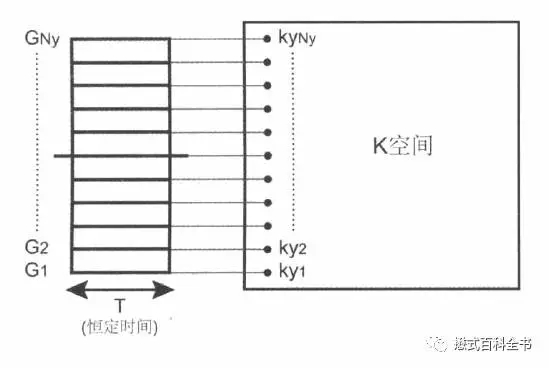

在MR图像采集过程中,每填充一条相位编码线,相位编码梯度都发生变化,而频率编码梯度并不变。

相位编码梯度变化一次,进行质子的相位编码方向(Ky)的定位。在频率编码方向上,一次信号采集,会采集很多的采样点,作为频率编码方向(Kx)的定位。

图5:相位编码梯度在采集信号之前就施加,施加了一定时间后,立即停止。这样保留了相位编码方向不同位置质子的相位差异。在信号采集的时候,相位编码梯度必须关闭。每一次相位编码梯度变化,采集一次信号,填充到一条相位编码线。

所以,如果相位编码方向分辨率越高(矩阵越多,阵列越多),就等于采集的相位编码线越多,每一次填充一条相位编码线,相位编码梯度都会变化,都会经过一个TR时间,这样的话扫描时间就和相位编码步级(填充到K空间的相位编码线)有关。

而在频率编码方向,一次采集的采样点越多,频率编码方向的阵列就越多,频率编码方向的分辨率越高。但是,一次采集,采样点多了,采集时间(Ts)并不会太明显的增加。所以,提高频率编码方向分辨率,有时候并不会增加扫描时间。